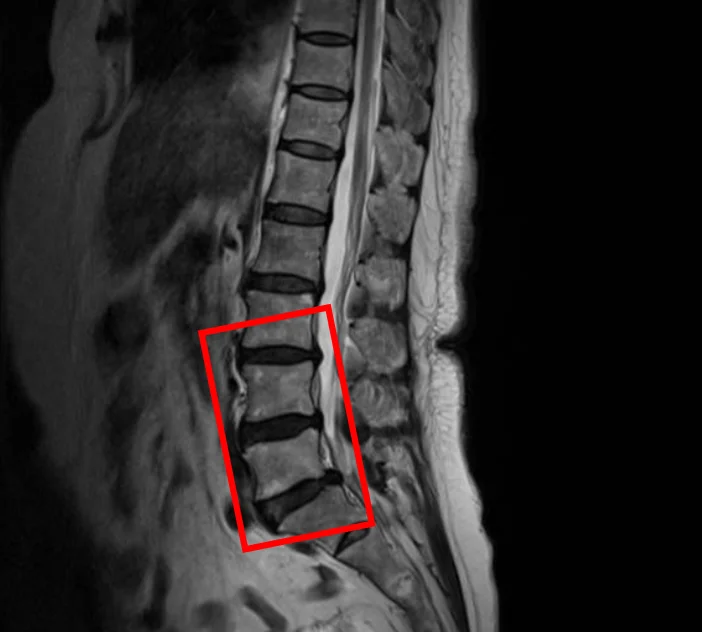

По данным МРТ и результатам осмотра пациентки выявлена дегенерация межпозвоночных дисков L3/L4, L4/L5, L5/S1.

В клинике проведена селлгель-терапия на 2 межпозвоночных дисках (L4/L5, L5/S1).